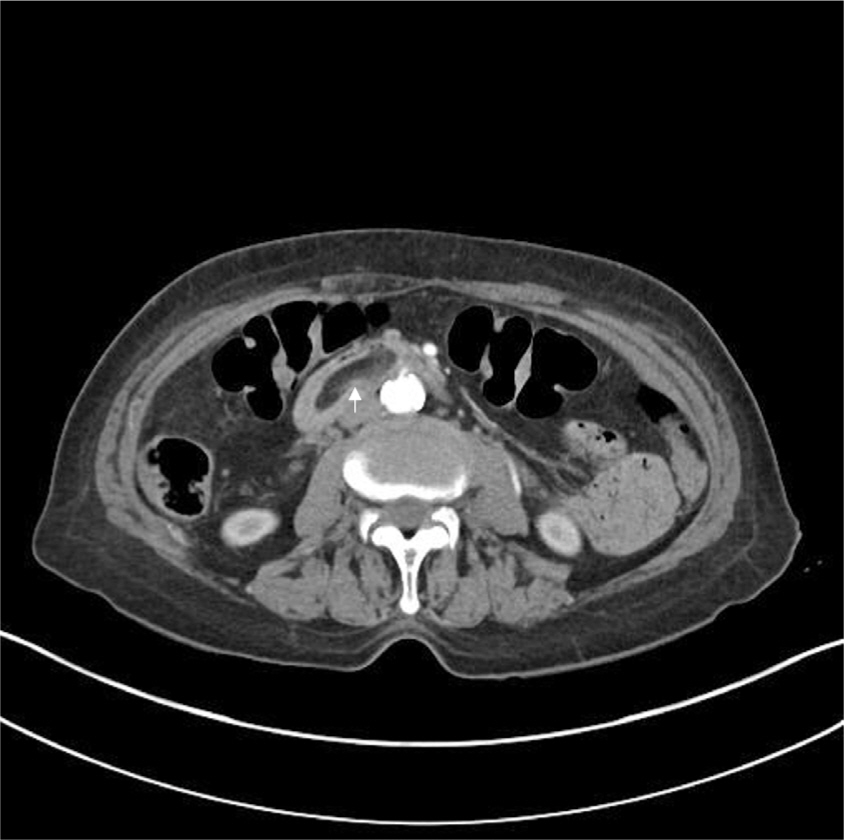

Initial CT scans revealed a 3-cm hypodense mass lesion, consistent with fat density, in the transverse portion of the duodenum (Fig. 1). Esophagogastroduodenoscopy showed a 3-cm SET in the third portion of the duodenum, with an active ulcer at its apex. Upon retraction of the duodenal lipoma, another ulceration with active bleeding was discovered on the opposite side of the lesion (Fig. 2). Consequently, immediate coagulation therapy was initiated. The patient reported that, while she had undergone endoscopic evaluation as part of Korea’s nationwide cancer screening program, she had not been told that she had a duodenal subepithelial lesion (SEL).

Fig. 1.

Abdominal CT revealed a hypodense mass in the third portion of the duodenum (indicated by the white arrow).

Fig. 1. Abdominal CT revealed a hypodense mass in the third portion of the duodenum (indicated by the white arrow).